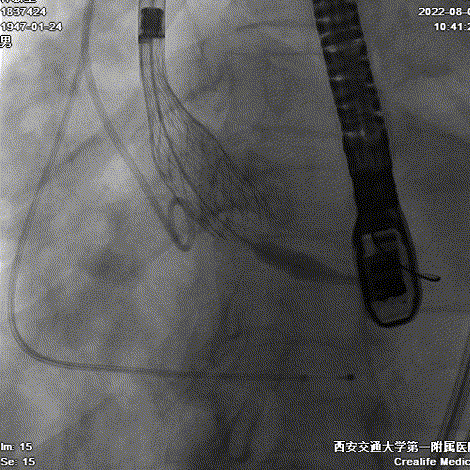

球囊预扩张

Evolut PRO 的递送系统对入路要求小,顺应性出色,装载瓣膜后仍能良好地顺应工作导丝形态,有效避免了对该患者降主动脉水肿部位的压迫,轻松抵达释放位置。

递送到达释放位